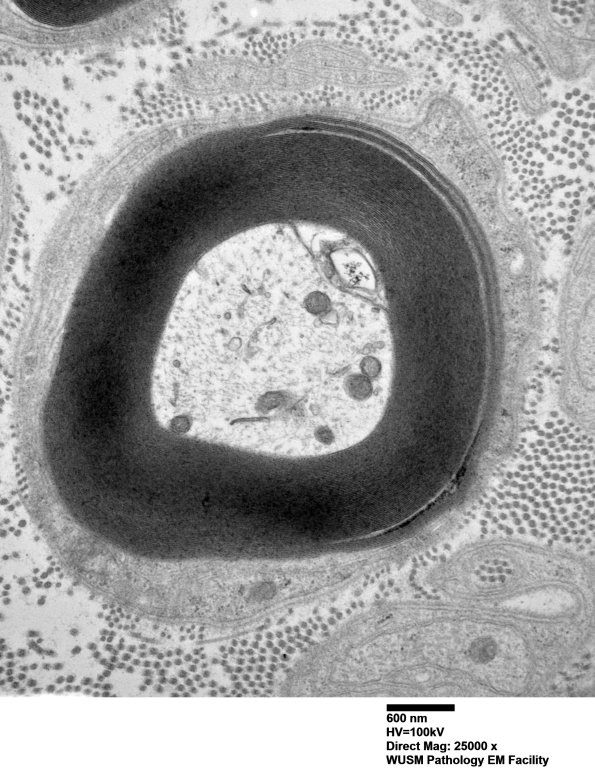

2B1A,B In distinction to the previous case, the number of axons with WSM is limited in extent of involvement of the myelin sheath and only occurs in rare axons. (electron micrographs)